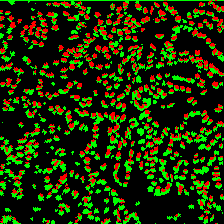

Microscopic image segmentation is a challenging task, wherein the objective is to assign semantic labels to each pixel in a given microscopic image. While convolutional neural networks (CNNs) form the foundation of many existing frameworks, they often struggle to explicitly capture long-range dependencies. Although transformers were initially devised to address this issue using self-attention, it has been proven that both local and global features are crucial for addressing diverse challenges in microscopic images, including variations in shape, size, appearance, and target region density. In this paper, we introduce SA2-Net, an attention-guided method that leverages multi-scale feature learning to effectively handle diverse structures within microscopic images. Specifically, we propose scale-aware attention (SA2) module designed to capture inherent variations in scales and shapes of microscopic regions, such as cells, for accurate segmentation. This module incorporates local attention at each level of multi-stage features, as well as global attention across multiple resolutions. Furthermore, we address the issue of blurred region boundaries (e.g., cell boundaries) by introducing a novel upsampling strategy called the Adaptive Up-Attention (AuA) module. This module enhances the discriminative ability for improved localization of microscopic regions using an explicit attention mechanism. Extensive experiments on five challenging datasets demonstrate the benefits of our SA2-Net model. Our source code is publicly available at \url{https://github.com/mustansarfiaz/SA2-Net}.